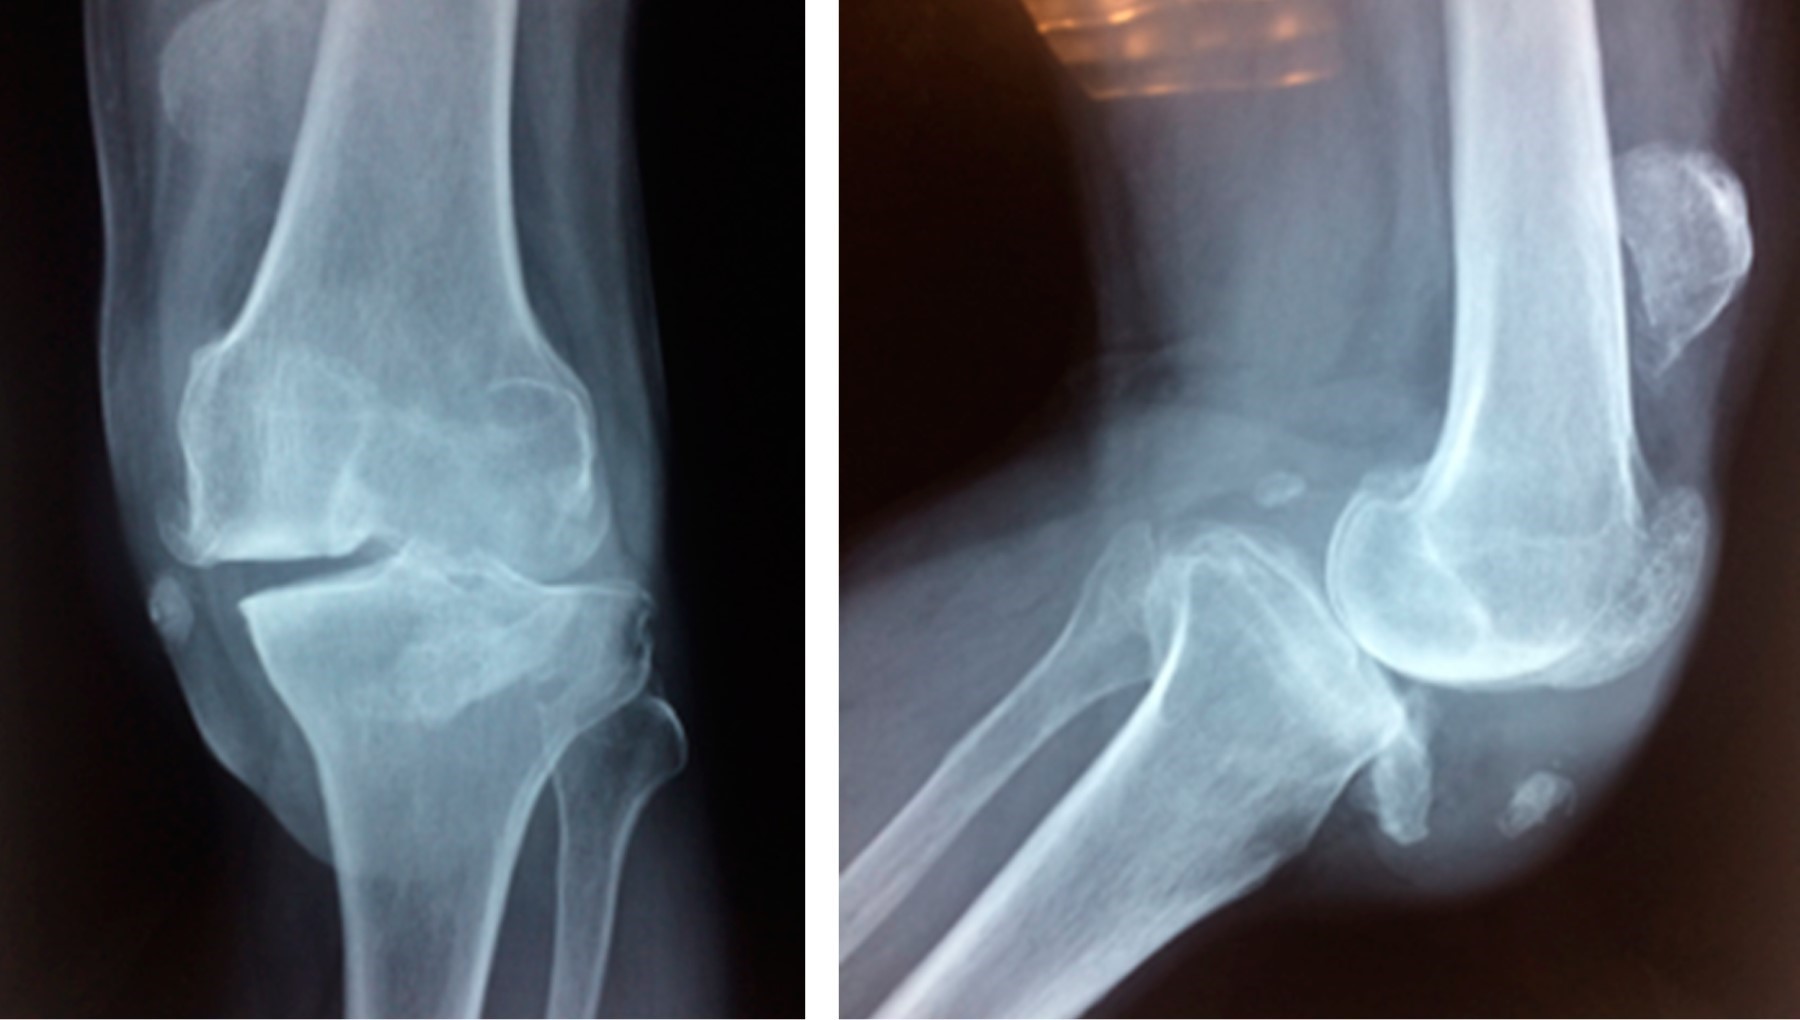

Se solicitó radiografía simple, encontrando en la proyección lateral fragmento avulsionado de tuberosidad tibial con migración proximal de rótula más cambios osteodegenerativos femorotibiales grado IV. En proyección anteroposterior se observa compartimento lateral con artrosis femorotibial grado IV (Figura 1). Se solicita eje mecánico encontrando deformidad en genu varo de 10o (Figura 2).

Se solicitó resonancia magnética donde se confirmó avulsión de tuberosidad tibial con fragmento óseo de tendón rotuliano más migración proximal de rótula en zona diafisiaria de fémur con artrosis fémoro-tibial grado IV.

Figura 1

Figura 2